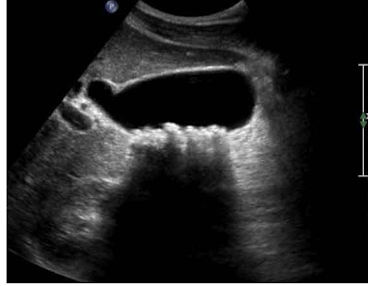

Cholecystitis, US

What is this and what type of scan